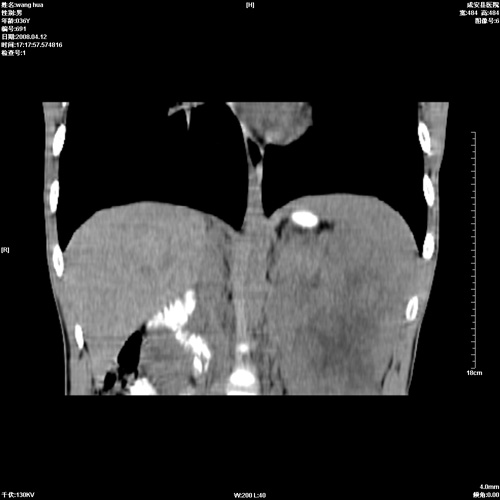

标题: CT12809:男36岁,自感上腹胀5天,B超诊断为脾肾之间占位,血 [打印本页]

标题: CT12809:男36岁,自感上腹胀5天,B超诊断为脾肾之间占位,血

请各位老师先分析一下定位 明天做增强

脾脏明显增大,其内见巨大低密度灶,境界不清,病史较短,考虑恶性病变脾血管内皮细胞肉瘤可能。建议增强扫描与脾脏淋巴瘤及血管瘤鉴别。